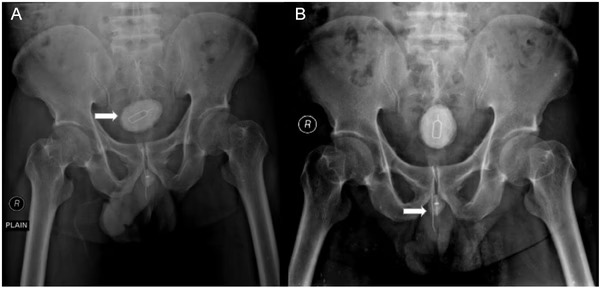

A radiografia revelou objetos estranhos, incluindo uma pedra na bexiga causada pelo objeto de metal. Durante a cirurgia, os médicos removeram uma pedra de 5×3 cm, além do cabo elétrico e uma agulha de 8 cm.